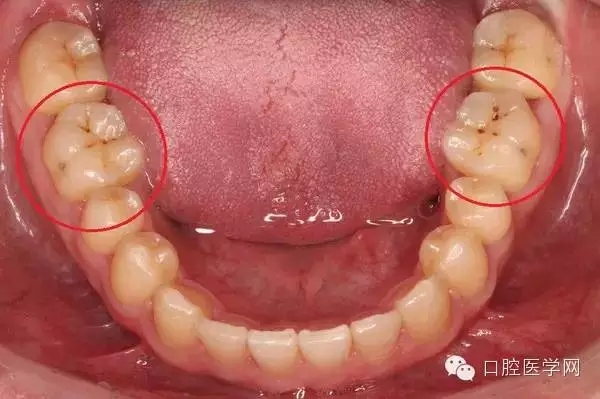

另一種則是牙齒出現(xiàn)了或深或淺的齲壞,從外面看就表現(xiàn)為一個(gè)黑點(diǎn),通常位于窩溝點(diǎn)隙(牙面上點(diǎn)狀或線狀凹陷)。齲齒的罪魁禍?zhǔn)资强谇恢械哪承┘?xì)菌,但它們破壞牙齒也是需要時(shí)間的,從初期的變色到最終形成齲洞,通常需要1年半到兩年。在此期間,我們多留心自己的牙齒,完全可能把齲壞扼殺在萌芽階段。如何才能及時(shí)發(fā)現(xiàn)這種隱匿的蛀牙呢?找位好牙醫(yī),半年檢查牙齒!